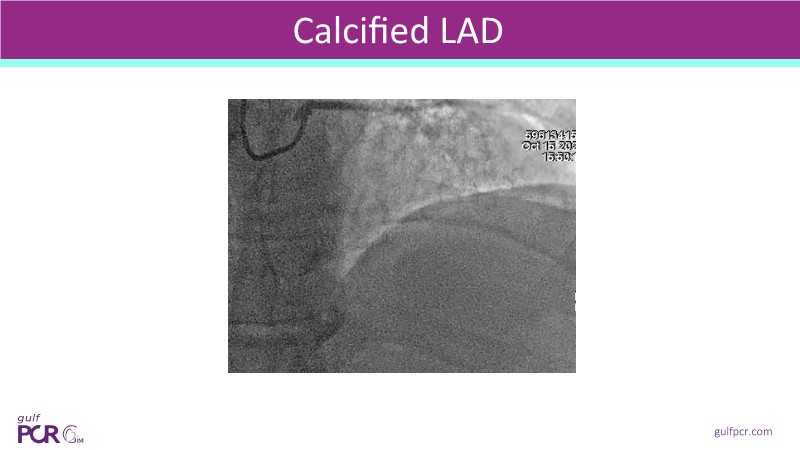

- To optimise lesion preparation: when NIRS reveals high lipid burden or calcific nodules, operators can choose atherectomy, intravascular lithotripsy, or specialised balloons to modify the lesion before stenting